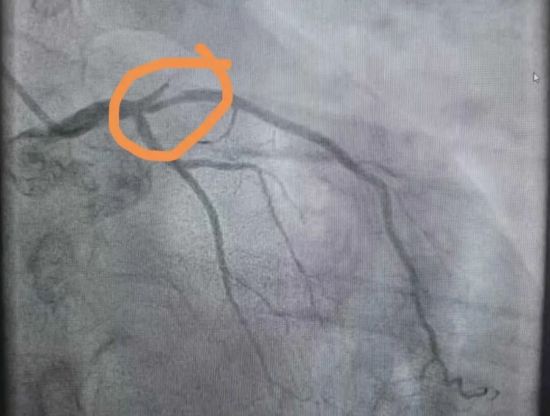

左前降支近段闭塞,回旋支严重狭窄

由于患者情况危急,医院立即启动胸痛中心绿色通道,导管室同步启动。随后,心血管内三科主任王爱华邀请哈尔滨市第二医院特聘专家周立君教授前来指导,梁庆辉医生与徐良医生共同为患者进行造影检查。检查过程中发现患者心脏左前降支近段闭塞,回旋支严重狭窄。在给予其球囊扩张、血栓抽吸等治疗后,胸痛症状逐渐缓解。因张先生术后突然出现右侧眼睑下垂,王爱华主任立即为其进行急诊颅脑CT检查,进一步排除了颅脑出血。患者既往有房颤病史,考虑眼睑下垂是因栓子脱落导致脑栓塞所致,随后转至心血管内三科继续治疗。